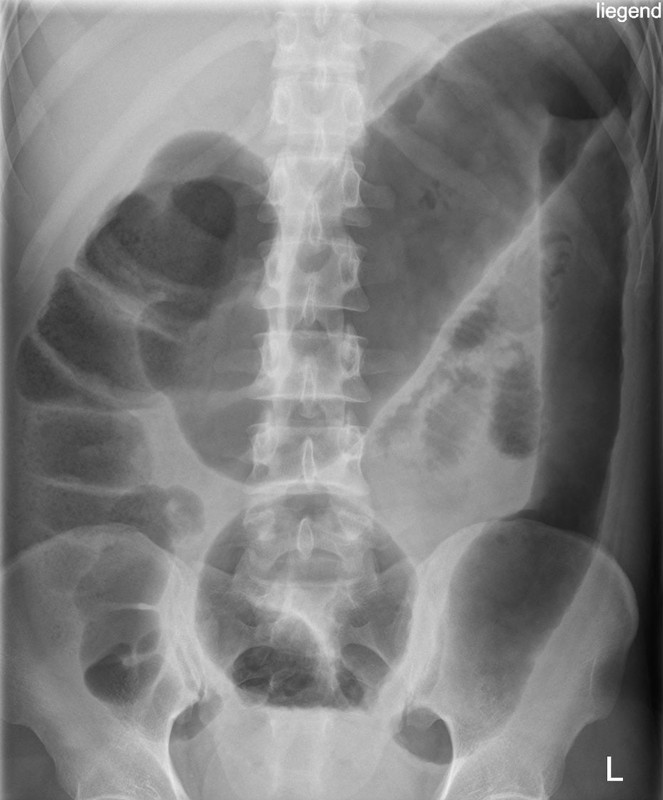

A 68-year-old woman presents to her primary care clinic for a follow-up visit, reporting a 3-day history of escalating gastrointestinal distress. She describes profuse, watery diarrhea, occurring 8-10 times daily, accompanied by diffuse cramping abdominal pain that intensifies before bowel movements. She notes some streaks of bright red blood on the toilet paper. This presentation began approximately five days after her discharge from the hospital, where she was treated for community-acquired pneumonia with prolonged courses of intravenous piperacillin-tazobactam. She denies recent travel or sick contacts. Her temperature is 38.1°C, blood pressure is 105/60 mmHg, pulse is 110/min, respirations are 18/min, and oxygen saturation is 97% on room air. On examination, she appears pale and fatigued, with dry mucous membranes. Abdominal palpation reveals generalized tenderness, particularly in the lower quadrants, with hyperactive bowel sounds. Cardiopulmonary examination is otherwise unremarkable. Given her history and clinical presentation, what is the most likely diagnosis and the most appropriate initial management plan?